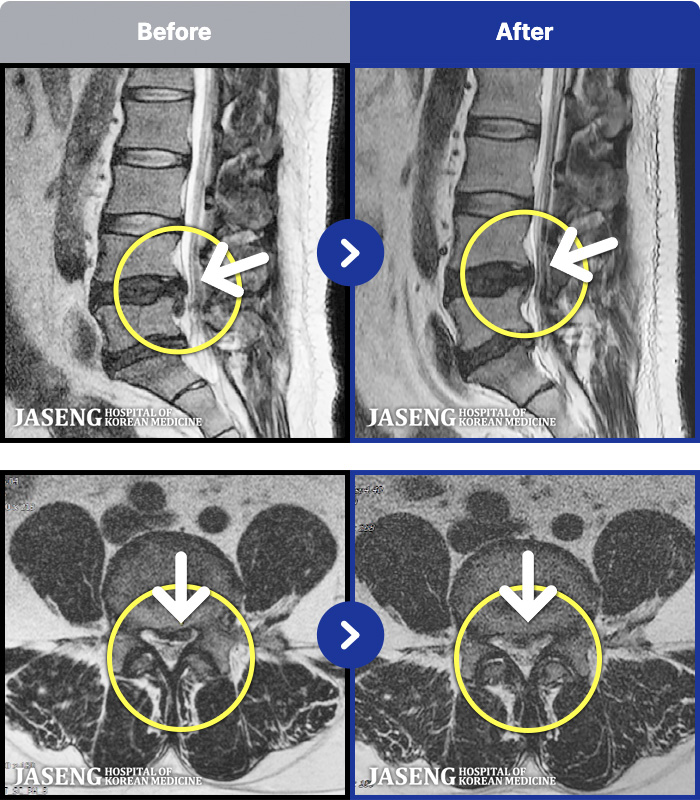

MRI ġ

56 MRI ũ ʸ Ȯϼ.